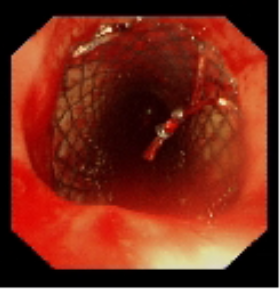

术中植入金属覆膜支架

针对患者气道狭窄危象,呼吸与危重症医学科联合麻醉科、医学影像科等多学科团队制定个性化方案。术中采用全身麻醉联合喉罩通气,通过硬质支气管镜与软镜协同操作,在狭窄段实施肿瘤冷冻切除,随后精准植入Y型金属覆膜支架。手术全程动态监测生命体征,最终支架释放位置理想,管腔扩张充分。术后复查显示气道通畅性恢复,患者血氧饱和度稳定在93%-97%。